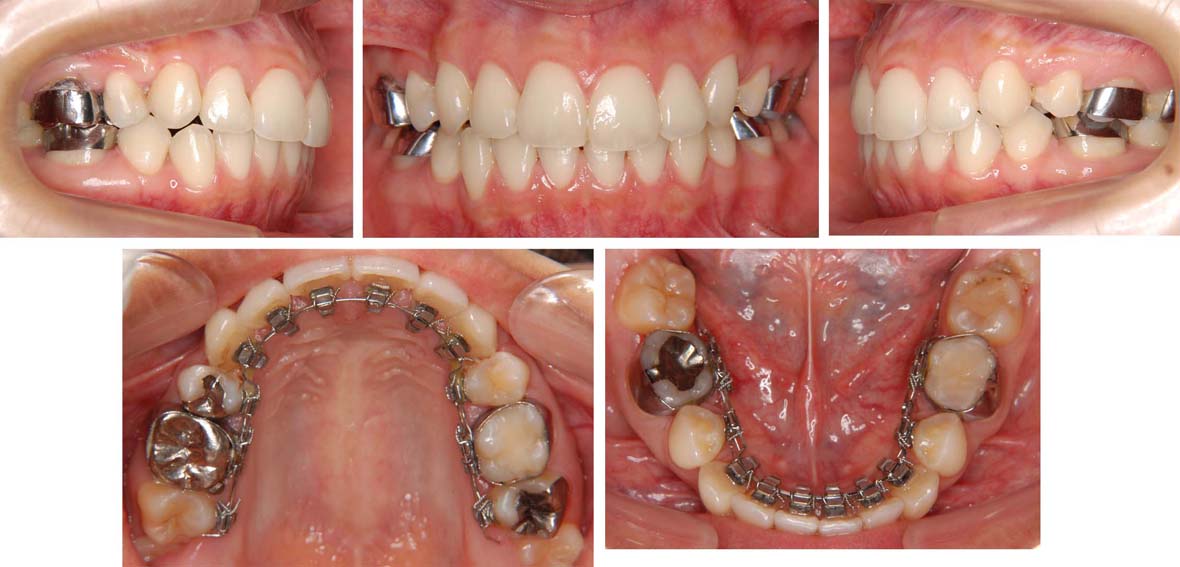

治療中の写真

もう少しでブラケットを外す事ができます。

これでちゃんと歯がみがきができます。新しいう蝕を作らないようにしてください。

口もとも内側に下がって、きれいな横顔をになりました。